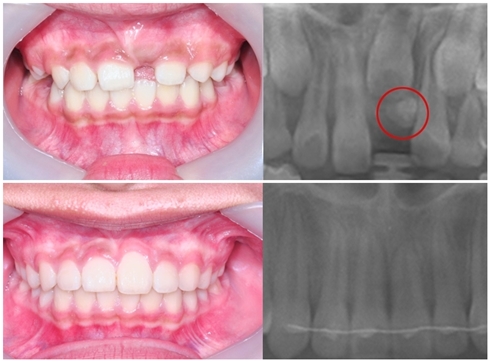

12¼¼ ¾ÆµéÀ» µÐ ¹Ú ¸ð¾¾(43¼¼). ¾ÆµéÀÇ À¯Ä¡°¡ °ÅÀÇ ´Ù ºüÁö°í ¿µ±¸Ä¡°¡ °¡Áö·±È÷ ¿Ã¶ó¿Í Å« °ÆÁ¤À» ÇÏÁö ¾Ê°í ÀÖ¾ú´Âµ¥ ¾î´À ³¯ È®ÀÎÇØ º¸´Ï ÇÑÂÊ ¼Û°÷´Ï°¡ ³ª¿ÀÁö ¾ÊÀº °ÍÀ» ¹ß°ßÇß´Ù. ÇÏÁö¸¸ ¼Û°÷´Ï°¡ ³¯¸¸ÇÑ ÀÚ¸®µµ ¾ø°í, ´Ù¸¥ Ä¡¾ÆµéÀº Àß ³ª°í Àֱ⿡ Ä¡¾Æ°¡ ³ªÁö ¾Ê°Ú°Å´Ï »ý°¢ÇÏ°í ´ë¼ö·ÓÁö ¾Ê°Ô »ý°¢Çß´Ù. ±×·±µ¥ ¸î °³¿ù ÈÄ ¾ÆµéÀÌ Ä¡¾Æ¿¡ ÅëÁõÀ» ´À²¸ Ä¡°ú¸¦ ã¾Æ ¿¢½º·¹À̸¦ Âï¾îº¸´Ï ¼Û°÷´Ï°¡ ¾ÈÂÊ¿¡¼ ´Ù¸¥ ¿µ±¸Ä¡µéÀ» ¹Ð¾î³»¸ç Ä¡¿¿¡ ¹®Á¦¸¦ ÀÏÀ¸Å°°í ÀÖ¾ú´Ù.

»çÁø. ¸Åº¹Ä¡ ±³Á¤ Àü(À§)°ú ±³Á¤ ÈÄ(¾Æ·¡)

¢¹ ¾à 11, 12¼¼ Àü, ÈÄ : ÀÌ ½Ã±â¿¡´Â ÀÅÎ ¼Û°÷´Ï ¸ÍÃâ¿¡¼ ÀÚÁÖ ¹®Á¦°¡ »ý±ä´Ù. ¼Û°÷´Ï°¡ ¸ÍÃâÇÏ¸é¼ ÁÖº¯ Ä¡¾Æ¸¦ ¹Ð¾î³»´Â µî ¿©Å¸ Ä¡¾Æ¿¡ ³ª»Û ¿µÇâÀ» ¹ÌÄ¡°Å³ª, ÀÕ¸ö ¿·À¸·Î ¸ÍÃâµÉ ¼ö ÀÖÀ¸¹Ç·Î(¼ÒÀ§ »µµå··´Ï¶ó°í ºÒ¸²) 11~12¼¼¿¡ ¼Û°÷´Ï°¡ ¸ÍÃâÀÌ ¾ÈµÇ¾úÀ» ¶§´Â ²À °Ë»ç°¡ ÇÊ¿äÇÏ´Ù.